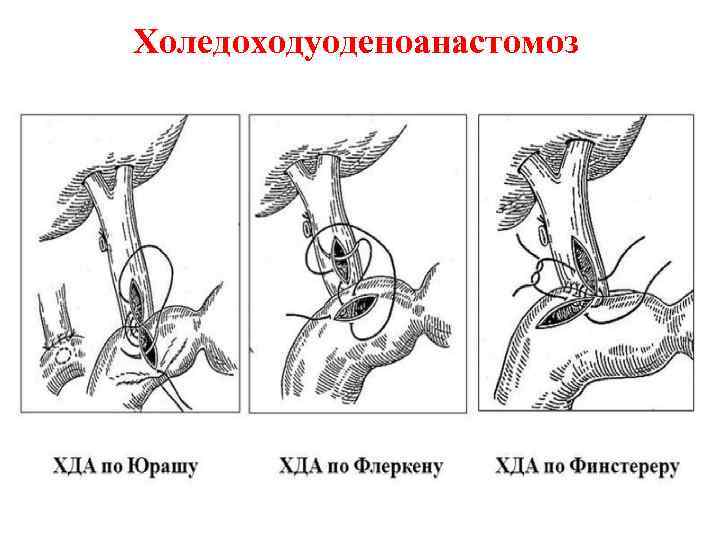

Холедоходуоденоанастомоз